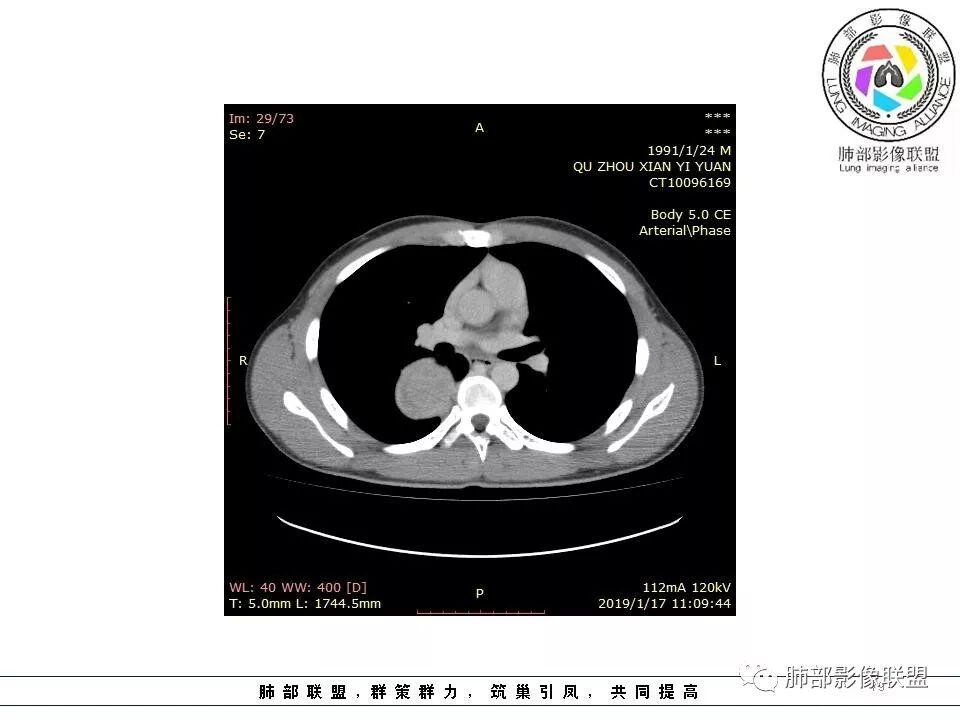

脏层胸膜主要由支气管动脉和肺动脉供血,壁层胸膜主要由支气管动脉,胸廓内动脉、肋间动脉供血

如果是肋间动脉,就不可能是脏层胸膜,可以是壁层或者纵膈

但是这个病人,肋间动脉供血吧,我倾向胸膜

肋间动脉供血,强化尚均匀,逐步强化

供血,体外供血,体循环,要么是壁层胸膜,要么胸膜外的,脏层胸膜应该是对内供血。病变里面的血管,除非是非常粗大迂曲的血管,不然,我不认为是其特点。

脏层胸膜肺内供血,壁层胸膜体外供血

这个病人不是肺动脉与支气管动脉供血,是肋间动脉供血